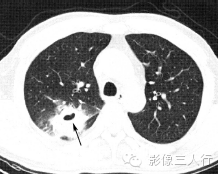

| 肺脓肿(图1) | 肺结核空洞(图2) | 癌性空洞(图3) | |

| 空洞形态 | 洞壁厚、模糊,内壁较光滑,内多见液平面 | 洞壁薄、内壁较光整,周围常有卫星灶 | 洞壁厚,多呈偏心性增厚,内壁常呈结节状 |

(A)平扫肺窗